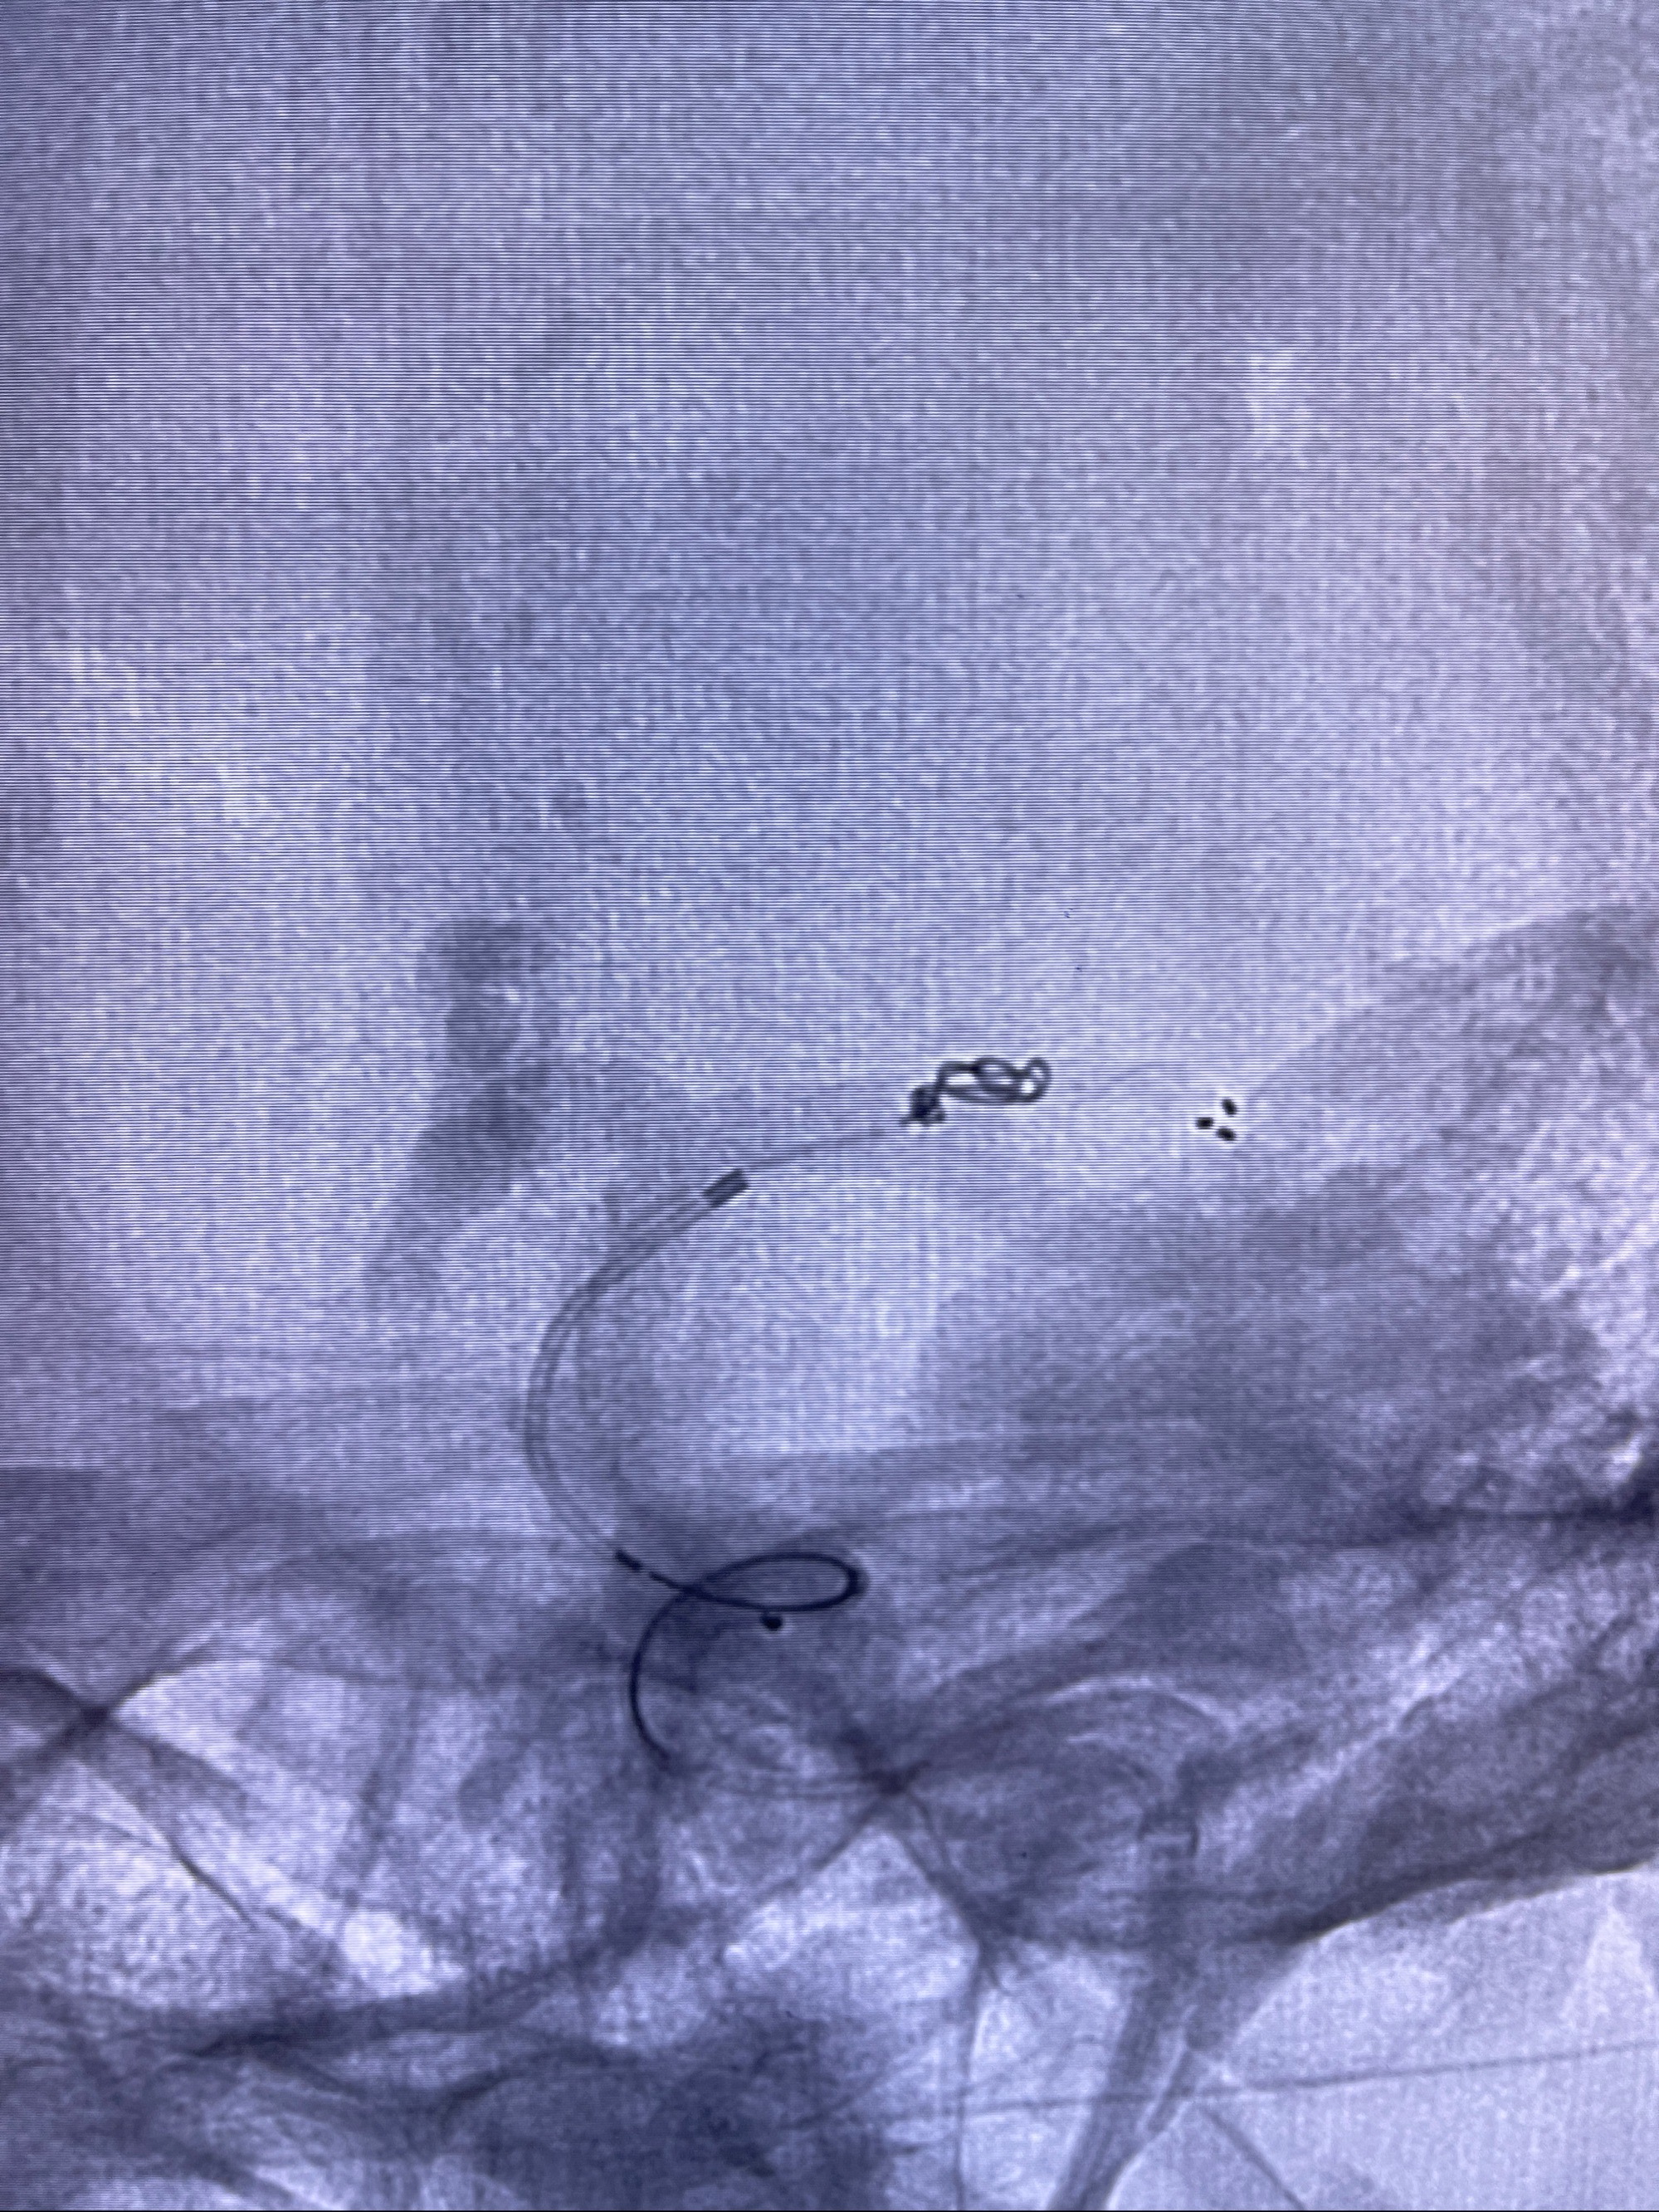

2.外科手术夹闭or介入支架辅助栓塞

麻醉苏醒佳,遵嘱动作